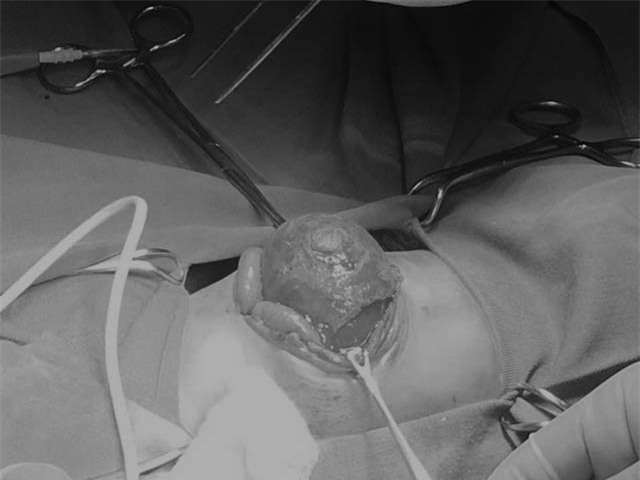

Ca phẫu thuật diễn ra trong khoảng hơn 40 phút, các bác sĩ tiến hành cắt bỏ toàn bộ tổ chức hoại tử trên bề mặt khối thoát vị, đưa khối ruột của bé vào đúng vị trí và tiến hành khâu phục hồi thành bụng 1 lớp cho trẻ.

Các bác sĩ đang tiến hành phẫu thuật cho bé T.